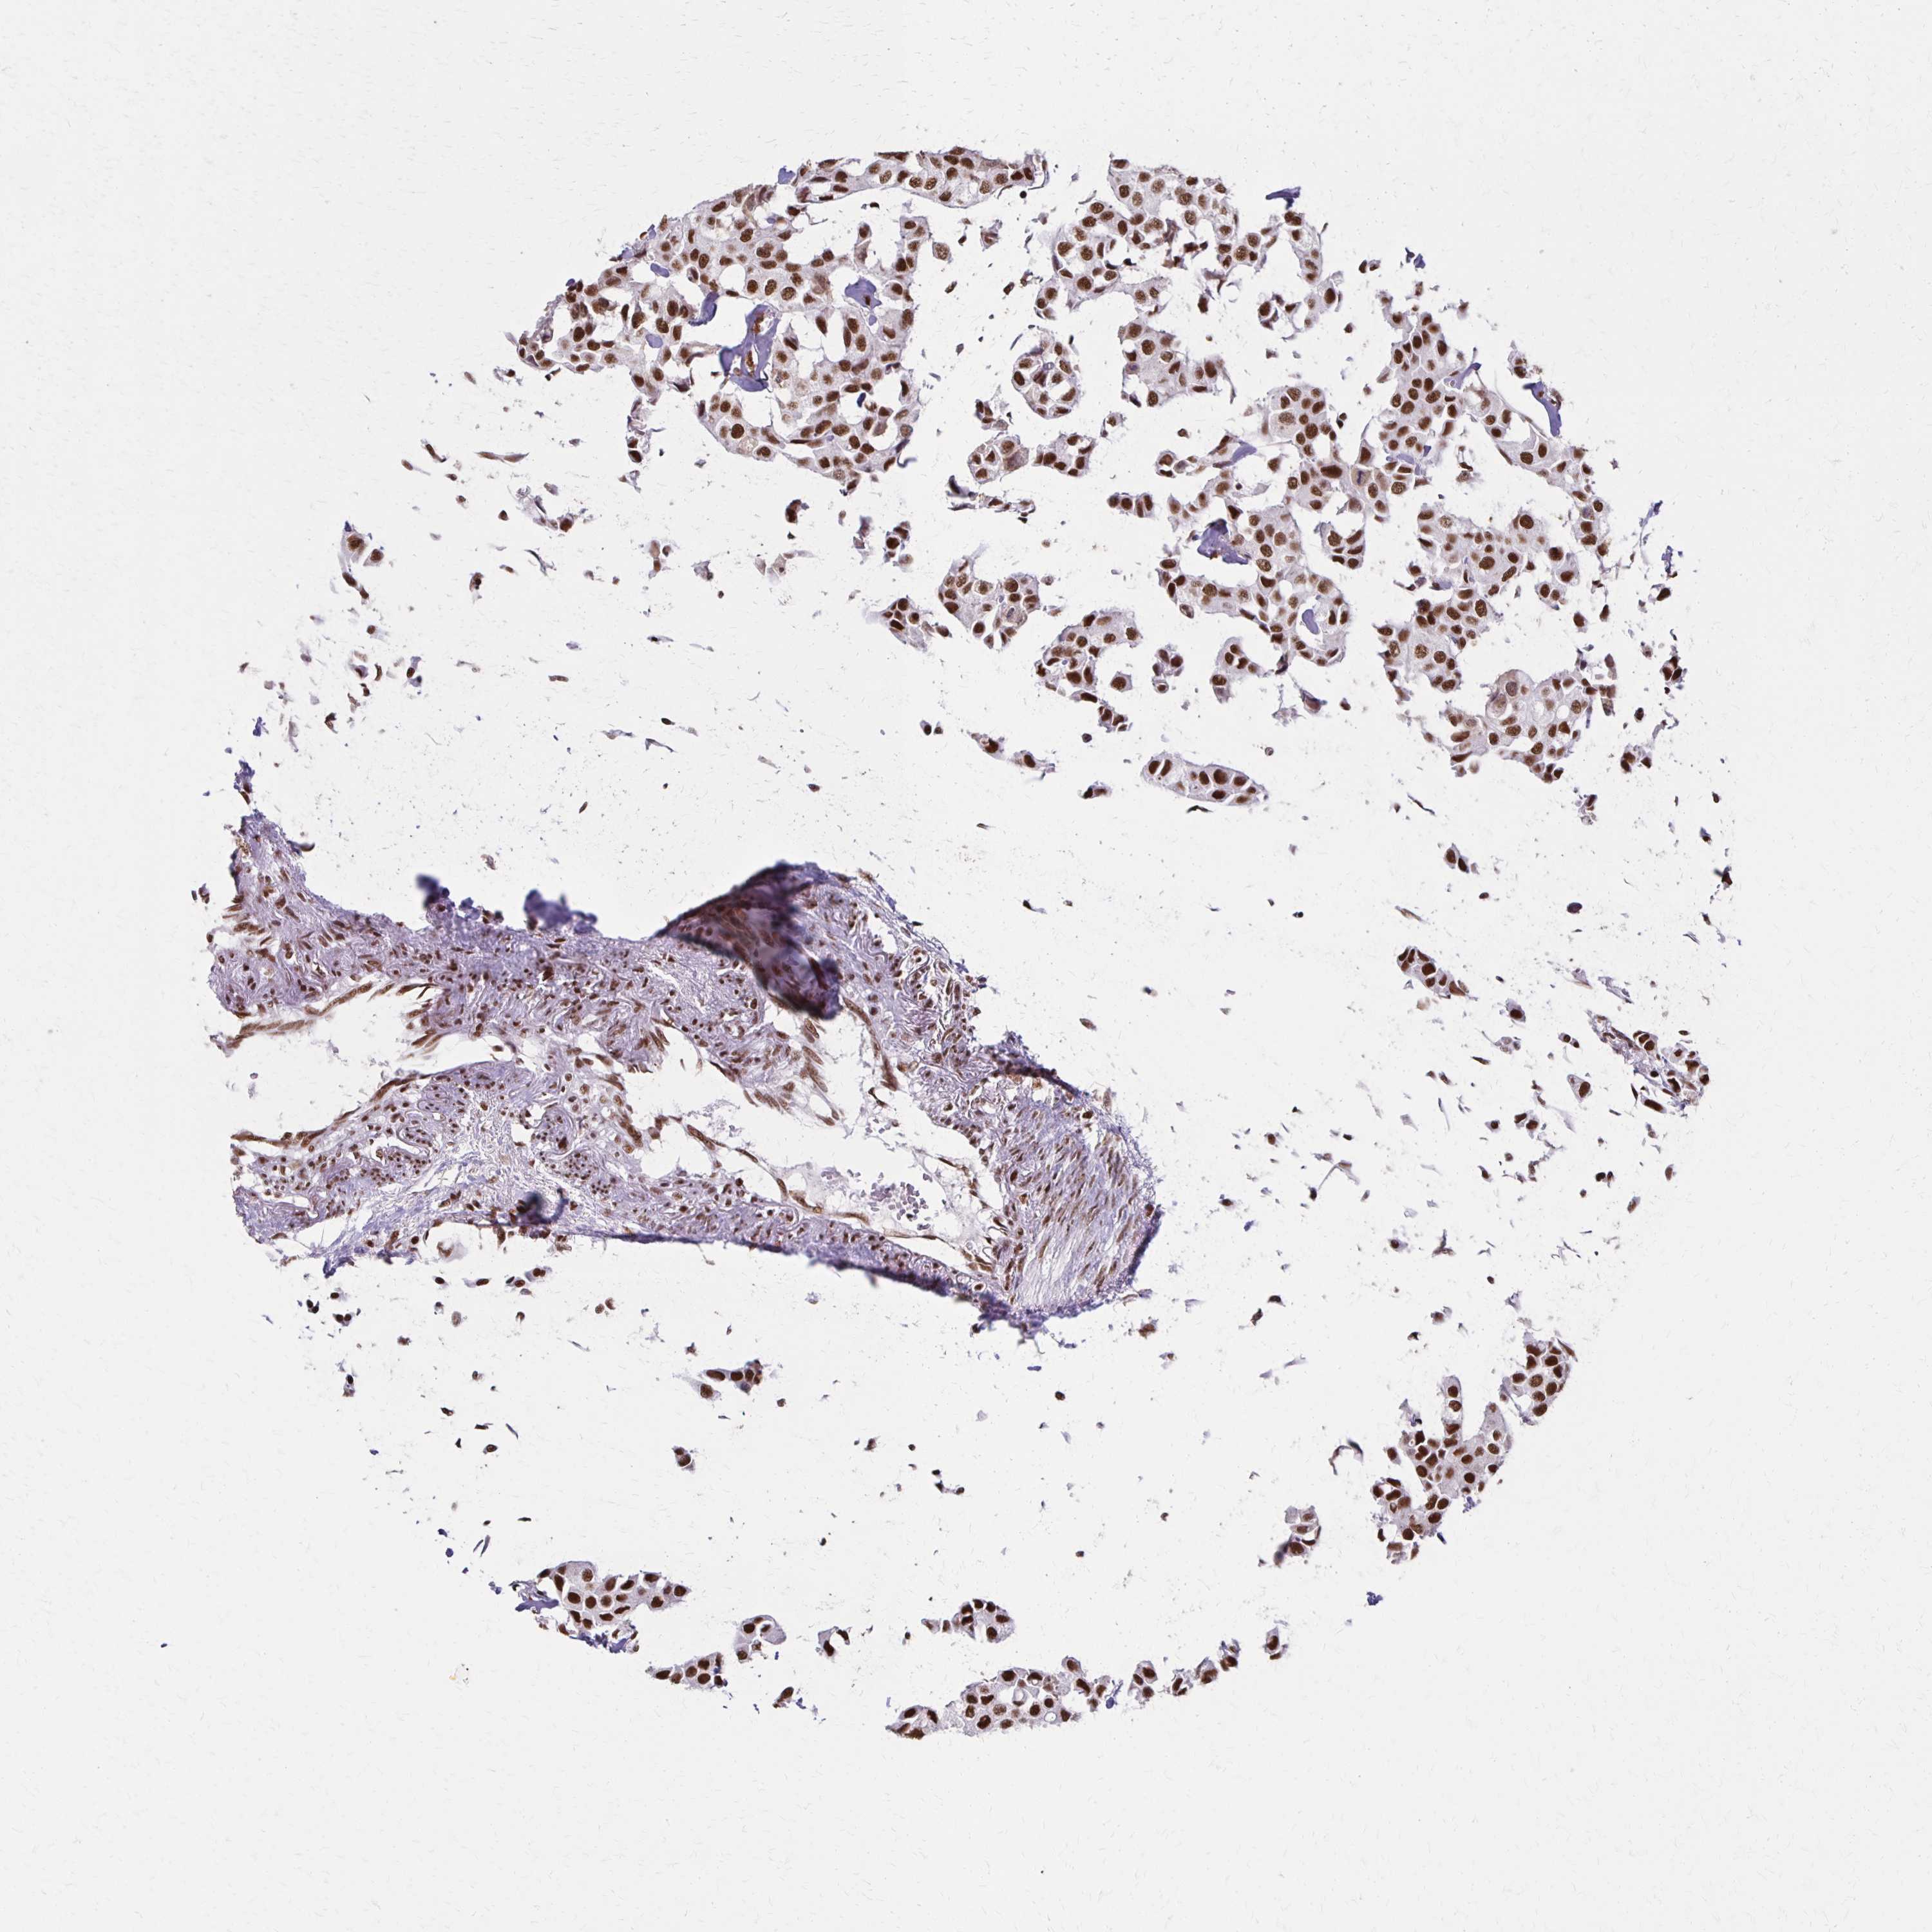

CANCER BREAST CANCER Show tissue menu

BRCA TCGA BRCA VALIDATION PROTEIN EXPRESSION

Breast cancer

Human cancer

Breast invasive carcinoma